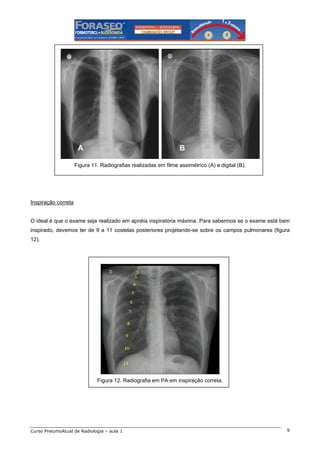

Dose de radiação

Não é raro encontrarmos exames muito ou pouco penetrados (figura 9). Idealmente, devemos ser capazes

de visualizar a sombra da coluna vertebral apenas nas suas porções mais superiores (figura 10). Exames

onde a coluna é visualizada na sua totalidade estão muito penetrados, a não ser que tenham sido

realizados em filmes especiais, ditos assimétricos, ou com sistema digital, onde é possível a visualização de

toda a coluna e das linhas mediastinais (figura 11).

A

B

Figura 11. Radiografias realizadas em filme assimétrico (A) e digital (B).

Inspiração correta

O ideal é que o exame seja realizado em apnéia inspiratória máxima. Para sabermos se o exame está bem

inspirado, devemos ter de 9 a 11 costelas posteriores projetando-se sobre os campos pulmonares (figura

12).

Figura 12. Radiografia em PA em inspiração correta.